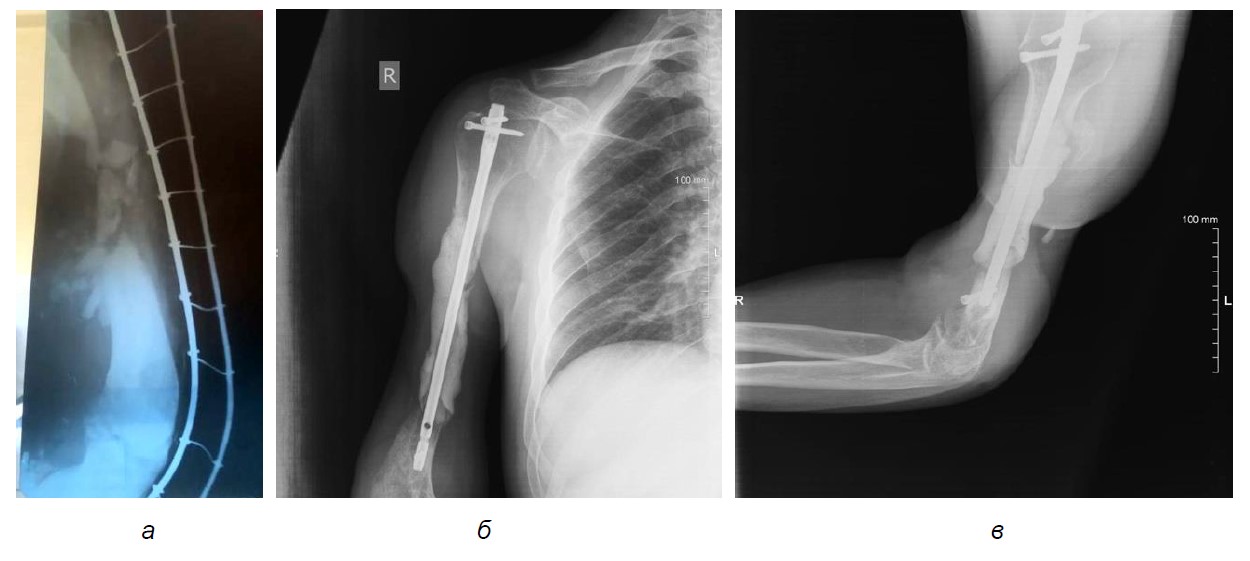

Пациент в результате минно-взрывной травмы получил многооскольчатый открытый перелом средней трети правой плечевой кости с дефектом костной ткани, наличием сквозной раны с размозжением мягких тканей (рис. 1а). Осложнением основного заболевания явилась посттравматическая невропатия правых срединного, лучевого, локтевого нервов с умеренным парезом правой кисти, до глубокого пареза за счет мышц разгибателей кисти с вегетативными нарушениями. Сведения о проведенном лечении представлены на основании выписок, имевшихся у пациента на момент обращения. В день ранения после оказания первичной помощи был доставлен в стационар, где выполнена первичная хирургическая обработка ран, фиксация правого плеча в стержневом аппарате наружной фиксации. Выполнялась вторичная хирургическая обработка ран с иссечением некротизированных тканей.

Рис. 1. Рентгенография правого плеча: а – после ранения, б – после установки спейсера (прямая проекция), в – после установки спейсера (боковая проекция)

После стабилизации состояния в ЦКБ Св. Алексия, митрополита Московского, на двадцатый день после ранения выполнен демонтаж аппарата внешней фиксации, вторичная хирургическая обработка открытого перелома, ревизия лучевого нерва; комбинированный и последовательный остеосинтез правой плечевой кости штифтом с блокированием с рассверливанием; установка цементного антибактериального спейсера (рис. 1б, в). В послеоперационном периоде проводилось лечение с использованием системы вакуумного дренирования. Проводилось несколько этапов вторичной хирургической обработки ран, наложения вторичных швов. Раны зажили с выраженными дефектами мышечной ткани (рис. 2).